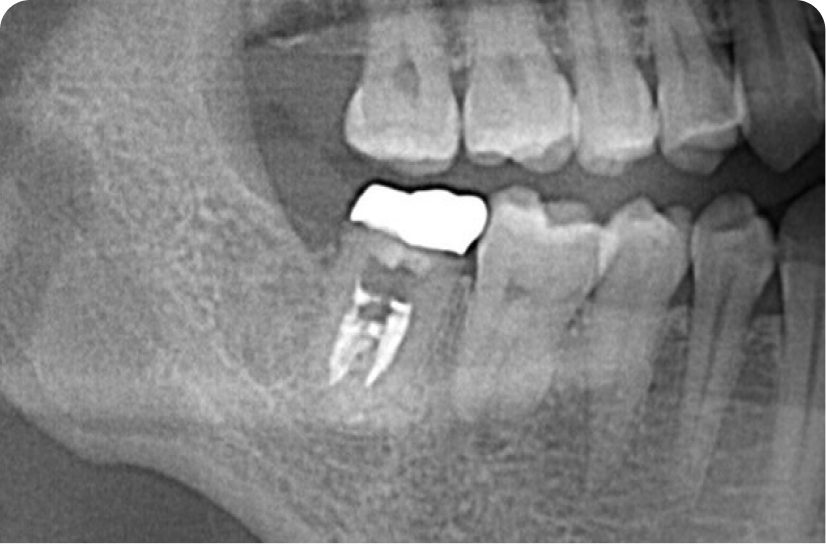

インプラントソケットリフト

他院で骨が少なくインプラントはできないと言われた60代男性の症例です。骨造成〜インプラントsetまで6〜12ヶ月、回数は、最短4回(抜糸・OBS除く)です。